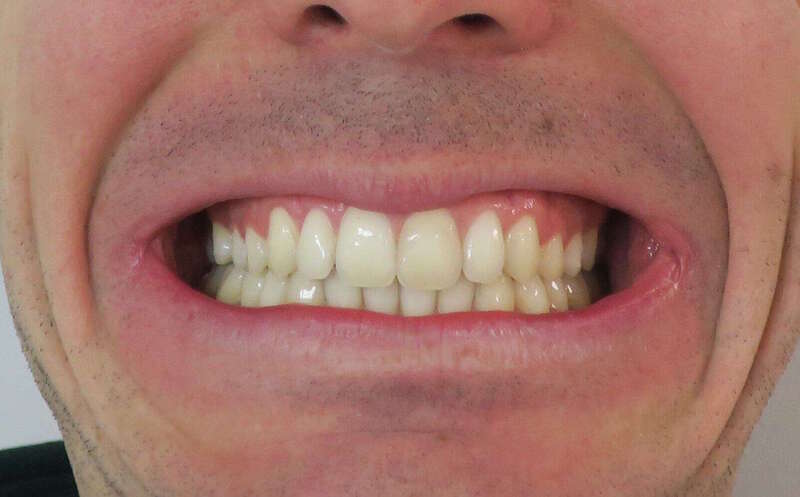

Cas n°1 d'orthodontie chirurgicale par aligneurs - adulte

Voici l'analyse de ce cas clinique concernant un patient adulte de 30 ans, illustrant la réussite d'un protocole ortho-chirurgical mené avec des aligneurs. Ce cas met en lumière l'importance de la fonction musculaire et respiratoire au-delà de l'alignement dentaire.

À 30 ans, la croissance est terminée, ce qui rend la correction d'un décalage osseux uniquement possible par la chirurgie :

• Rétrognathie Mandibulaire (Profil Rétrusif) : Le patient présentait un menton fuyant, caractéristique d'une mandibule trop courte ou positionnée trop en arrière.

• Déficit Fonctionnel : L'absence d'engrènement correct entraînait une mastication inefficace. Le patient rapportait une sensation de "manque de force" lors de l'alimentation.

• Supraclusion et Décalage : Un recouvrement incisif important qui bloquait toute dynamique mandibulaire saine.

• Usure et Fatigue : Chez l'adulte, ces malpositions entraînent souvent des tensions musculaires et une usure prématurée du capital dentaire.Le traitement a combiné la précision numérique des aligneurs et la puissance de la chirurgie maxillo-faciale :

1. Préparation par Aligneurs : Les arcades ont été préparées (alignement et coordination) pour que, une fois la mâchoire avancée par le chirurgien, les dents s'emboîtent immédiatement.

2. Avancée Mandibulaire Chirurgicale : Le repositionnement osseux a permis de corriger le profil de manière spectaculaire, redonnant de la force et de la structure au bas du visage.

3. Réhabilitation de la Force Masticatrice : C'est le point clé du ressenti patient. En retrouvant un engrènement de Classe I, les muscles masticateurs travaillent enfin avec un rendement optimal. Le patient ressent physiquement ce retour de puissance musculaire.

4. Harmonie du Profil : L'avancée du menton a équilibré les proportions du visage, offrant un profil plus affirmé et une meilleure définition de la ligne mandibulaire.